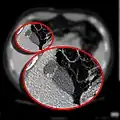

CT scan showing a phrygian cap CT scan showing a phrygian cap

In medicine, a Phrygian cap is the folded portion of some gallbladders that resembles the Phrygian cap (a soft conical cap with the top pulled forward, associated in antiquity with the inhabitants of Phrygia, a region of central Anatolia). It is a normal anatomical variant seen in 1-6% of patients.[1] It is caused by a fold in the gallbladder where the gallbladder fundus joins the gallbladder body.[2] Apart from the chance of being mistaken for stones on a sonogram, it has no other medical implications nor does it predispose one to other diseases. However, due to potential decrease in bile flow, it may warrant a preventive removal of the gallbladder.